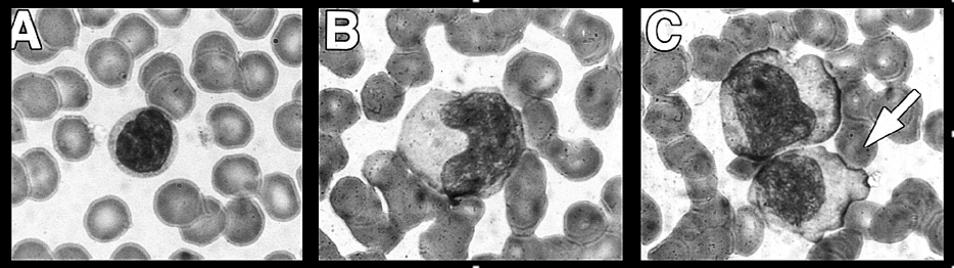

• Atypical lymphocytes [Fig] usually comprise 10-30+% of circulating lymphocytes.

Atypical Lymphocytes

A. Normal Lymphocyte

B. Enlarged, atypical lymphocyte with more cytoplasma and bilobed nucleous

C. So-called "Dutch Skirting" caused by red blood cells indenting lymphocyte outer membrane